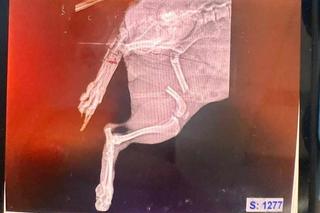

Mieszkanka Raciborza w piątkowy wieczór około godziny 20:00 przechodziła razem ze swoim 7-letnim wnuczkiem i psem przez park im. Miasta Roth, kiedy podbiegł do nich agresywny czarno-biały pies w typie amstaffa. Duży pies rzucił się do ataku i pogryzł zaledwie 2-letnią suczkę rasy chihuahua o imieniu Milka. Suczka w bardzo ciężkim stanie trafiła do kliniki weterynaryjnej, gdzie rozpoczęto walkę o jej życie. Do tej pory znajduje się pod opieką specjalistów i wciąż nie wiadomo, czy jej stan się poprawi.